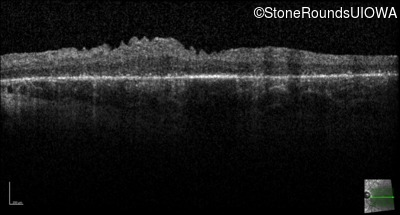

| Age at visit: 23 years |